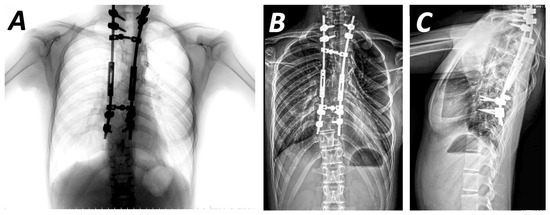

Tips and Pitfalls of Surgical Techniques for Scoliotic Deformities in Neurofibromatosis Type 1

by Angelos Kaspiris, Ioanna Lianou, Vasileios Marouglianis, Roberta-Spyridoula Afrati, Evangelos Sakellariou, Andreas Morakis, Panagiotis Karampinas, Elias S. Vasilisadis and Spiros G. Pneumaticos

J. Clin. Med. 2026, 15(1), 104; https://doi.org/10.3390/jcm15010104 - 23 Dec 2025

Background: Neurofibromatosis 1 is an autosomal dominant disorder accompanied by extensive early-onset spinal manifestations, with or without dystrophic scoliotic features. While non-dystrophic subtypes can often be treated similarly to idiopathic scoliosis, dystrophic scoliosis typically requires more aggressive intervention, often involving instrumentation in [...] Read more.

Background: Neurofibromatosis 1 is an autosomal dominant disorder accompanied by extensive early-onset spinal manifestations, with or without dystrophic scoliotic features. While non-dystrophic subtypes can often be treated similarly to idiopathic scoliosis, dystrophic scoliosis typically requires more aggressive intervention, often involving instrumentation in severely compromised pedicles or vertebrae. Purpose: This review aims to present recent advances in the surgical treatment of Neurofibromatosis 1-associated scoliosis, including surgical techniques and emerging guidance methods. Methods: An electronic literature search was conducted in Web of Science and PubMed to identify surgical techniques for scoliosis in patients with Neurofibromatosis 1. Results: Forty-one studies on the operative treatment of dystrophic scoliosis or both subtypes were retrieved. Although aggressive treatment with combined anterior and posterior fusion are widely used, posterior-only methods, which avoid plexiform tumours, present encouraging results. Recent studies highlight the effectiveness of growing rod systems in early-onset cases, enabling delayed fusion while preserving T1-S1 growth. Promising results from sectional or segmented correction techniques demonstrate better sagittal balance and Cobb angle correction, respectively. Preoperative use of halo-gravity traction, which has been extensively studied, is associated with reduced neurological impairment and encourages better correction results, avoiding autofusion. Various studies have also reported more precise pedicle screw placement with guidance of O-arm and triggered electromyography (t-EMG). Conclusions: The correction of spinal scoliotic deformities presents a significant challenge. However, recent advances in surgical techniques and intraoperative guidance offer promising strategies for more effective management. Full article